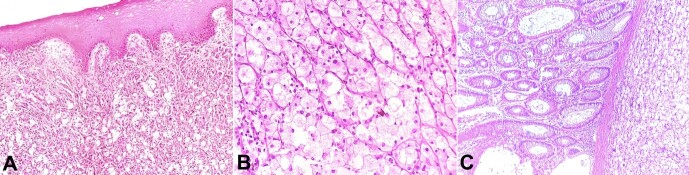

气球细胞黑色素瘤是一种罕见的恶性黑色素瘤,通常发生在皮肤上,报道的病例不到 100 例。粘膜球形细胞黑色素瘤更为罕见,英文文献中仅有一例肛门直肠球形细胞黑色素瘤的报道。诊断的依据是组织病理学发现的由大的泡沫状黑色素细胞组成的肿瘤,伴有或不伴有色素沉着,并经免疫组化研究证实显示黑色素细胞标记物的表达。肿瘤细胞的泡沫细胞外观和黑色素色素的缺乏导致了诊断上的两难,尤其是在肿瘤位置不寻常的情况下。在此,我们报告了一例肛门直肠交界处的气球细胞黑色素瘤病例,患者 73 岁,男性,主诉便秘和直肠出血。经过三年的密切随访,手术切除后无复发迹象。我们相信这个病例将提高医学界对直肠肿块的鉴别诊断意识。

Balloon cell melanoma is a rare presentation of malignant melanoma, usually on the skin, with less than 100 cases reported. Mucosal BCM is even rarer, with only one case of anorectal BCM reported in English literature. The diagnosis is based on the histopathologic findings of a tumor composed of large, foamy melanocytes, with or without pigmentation, and confirmed by immunohistochemical studies showing expression for melanocytic markers. The foam cell appearance of the tumor cells and the lack of melanin pigment lead to a diagnostic dilemma, mostly when presented at an unusual location. Herein, we report a case of balloon cell melanoma at the anorectal junction in a 73-year-old male patient complaining of constipation and bleeding per rectum. Surgical resection was performed with no evidence of recurrence after three years of close follow-up. We believe this case will raise awareness among the medical community to consider this tumor a differential diagnosis in rectal masses.